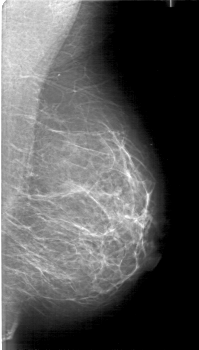

D_4071_1.RIGHT_MLO

RIGHT_MLO LINES 5266 PIXELS_PER_LINE 2986 BITS_PER_PIXEL 12 RESOLUTION 43.5 OVERLAY